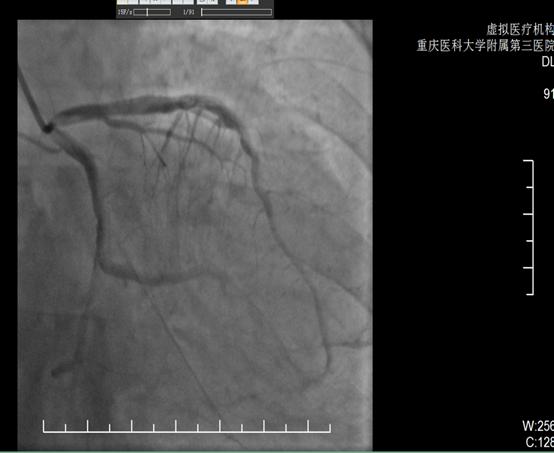

pic术前

pic术后